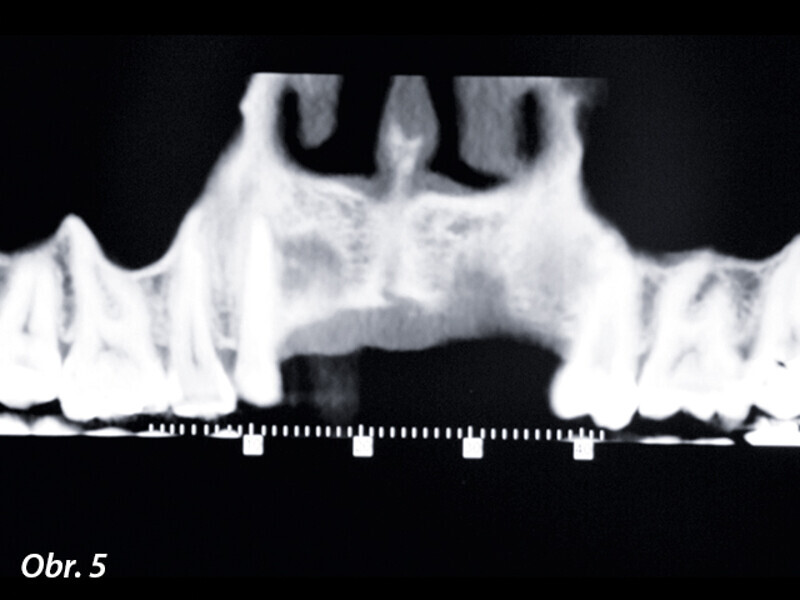

Opětovné implantologické ošetření